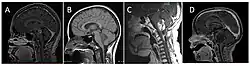

Brain stem glioma. MRI axial, with contrast | |

_-_Fonc-02-00205-g003_D_(cropped).jpg)

Neuroimaging, such as MRI, is the main diagnostic tool for brain stem gliomas. In very rare cases, surgery and biopsy are performed.